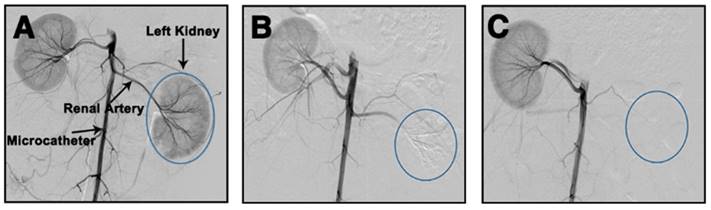

Figure 3

DR images of rabbit abdomens immediately, 1 week, 2 weeks, 3 weeks and 4 weeks after embolization of the left kidney with (A-E) Ta@CaAlg or (F-J) CaAlg microspheres. The areas marked by the red circles are left embolized kidneys.

Ta@CaAlg microspheres can not only provide visualization of the process of embolization, but also solve problems associated with patient re-examination after TCAE procedures. Normally, patients undergoing TACE require repeated intravenous injections of contrast media at designated time intervals to track their embolization status using contrast-enhanced CT. Since Ta@CaAlg microspheres are “2-in-1” agents that should not leak their contrast media, they are inherently long-term radiopaque microspheres. Using clinical imaging modalities such as DR and CT, Ta@CaAlg embolic microspheres should be directly visible within the vasculature over prolonged periods without the need for any additional injections of contrast media. This would dramatically improve the quality of patients' life and decrease treatment cost. As shown in Figure 3, the DR images of rabbits' kidneys embolized with Ta@CaAlg microspheres clearly exhibited embolized arteries. The embolized vessels were as clearly visible under X-ray over the 4 weeks of the study as they were immediately after injection. These results suggest that the X-ray opaque property of Ta@CaAlg microspheres is very stable in vivo. Pure calcium alginate microspheres lacking Ta NPs (CaAlg) were used as a control. Although the arteries were embolized by these microspheres, they did not exhibit any trails of occluded vessels in the DR images at the different time points.